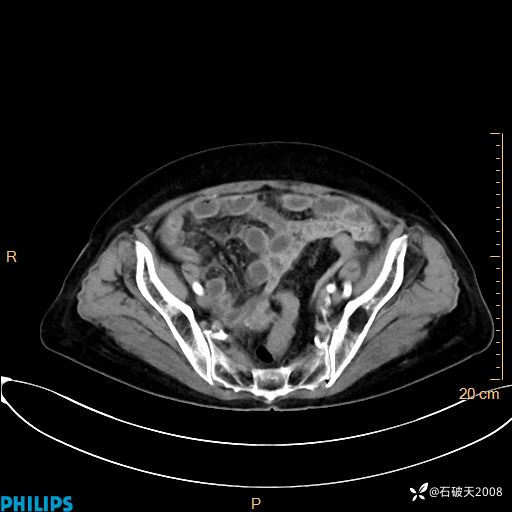

动脉期